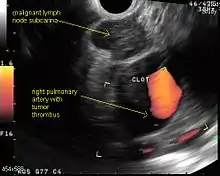

| Endoscopic ultrasound (EUS) | Least invasive modality, uses the esophagus to access mediastinal lymph nodes, excellent for station 5, 7, 8 lymph nodes. Useful for station 2L and 4L, L adrenal, celiac lymph node | Cannot reliably access right sided paratracheal lymph node stations 2 R and 4R; accurate discrimination of primary hilar tumors and involved lymph nodes is important |

Endoscopic ultrasound (EUS) is an endoscopic technique where a miniaturized ultrasound probe is passed through the mouth into the upper gastrointestinal tract to investigate organs and structures close to the esophagus, stomach, or duodenum, such as the lung. In 1993, Wiersema published the first description of EUS to diagnose and stage lung cancer,[27] done by advancing a fine needle through the esophagus into adjacent lymph nodes. Numerous subsequent studies have shown this general methodology to be effective, very safe, minimally invasive, and very well tolerated. Given these advantages, many authorities think that EUS together with endobronchial ultrasound (EBUS) enhances lung cancer diagnosis and staging.[28]

Endoscopic ultrasound (EUS)

EUS can reliably reach the lymph node stations 5, 7, 8 and 9. In the superior mediastinum the trachea is somewhat to the right of the esophagus which makes it often possible to reach left-sided area 2 and 4 lymph nodes and, less often, right sided paratracheal lymph nodes.[29] In general, EUS is most appropriate for evaluation of the posterior inferior mediastinum while mediastinoscopy or EBUS are best for the anterior superior mediastinum. The feasibility of EUS-FNA of aorto-pulmonary space (subaortic) lymph nodes (station 5) is a major advantage of EUS. Evaluation of this station has traditionally required a paramedian mediastinotomy (Chamberlain procedure). EUS can easily sample celiac lymph nodes, which cannot be reached by the other mediastinal staging methods. In one recent study an unexpectedly high incidence of celiac lymph node metastasis (11%) was noted.[30] EUS can also be used to biopsy potential left adrenal metastases, whereas the right adrenal gland is mostly inaccessible.[31]